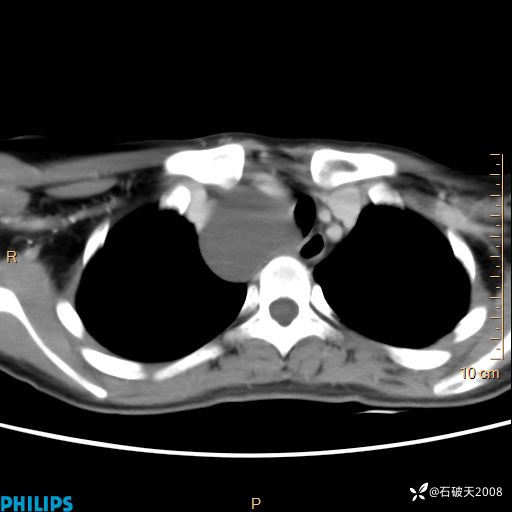

影像诊断要密切结合临床,真的很有必要(病理已公布)

女 21岁 主 诉:发现右侧颈部肿物18年余。

现病史:18年余前患者无明显诱因发现颈部偏右侧有一肿物,具体大小不明确,咳嗽、憋气时肿物增大,局部无疼痛,无吞咽不适,无胸闷及呼吸困难,至当地医院检查考虑良性病变(具体不详)并未做特殊处理,现患者自觉肿物随年龄增长而进一步变大,今日至我院行颈部CT平扫+增强提示:1.右侧颈根部、锁骨上窝及纵隔内异常密度影,考虑良性病变,淋巴管瘤?囊肿?请结合临床。2.双侧颈部小淋巴结。建议结合临床及其他相关检查。现为行进一步治疗,门诊以“颈部局部肿物”为诊断收住我科,发病来患者神志清,精神可,饮食睡眠可,大小便正常,体重无下降。

静脉期